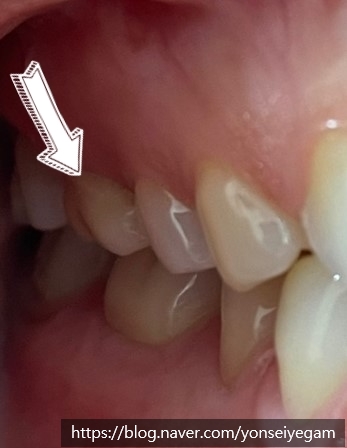

화살표 한 치아인데 크라운이 씌워져 있다고 믿기지 않을만큼 감쪽같죠?